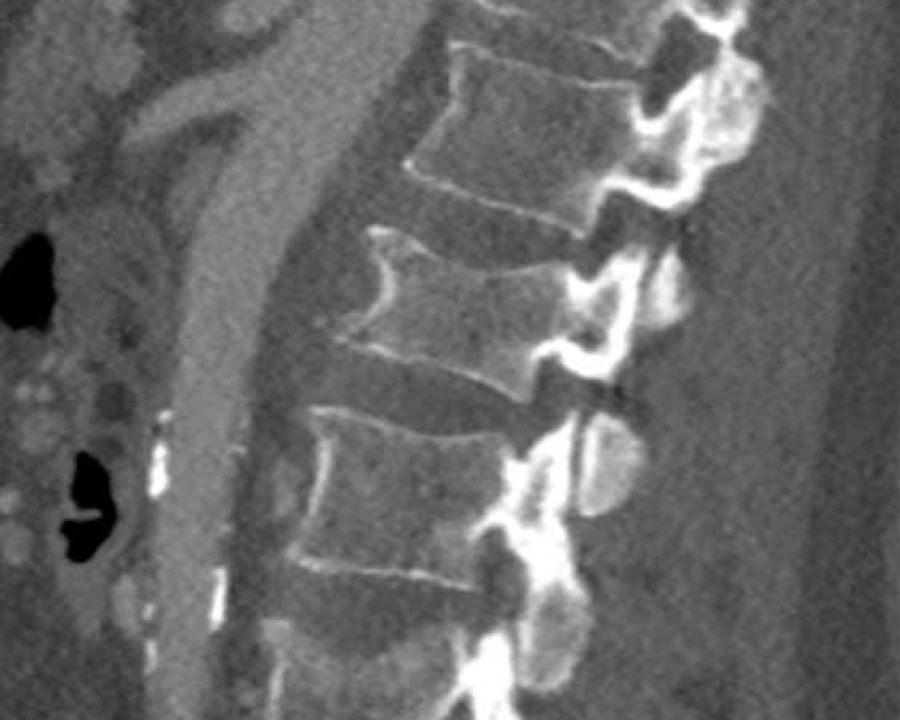

A2 Split fracture

A2 is a fracture of both endplates without involvement of the posterior wall of the vertebral body.

What is the highest AO-type of injury?

Findings:

- No C or B injury

- Fracture of the vertebral body with involvement of both endplates (1+1 points), no posterior wall involvement

Conclusion

injury type A2